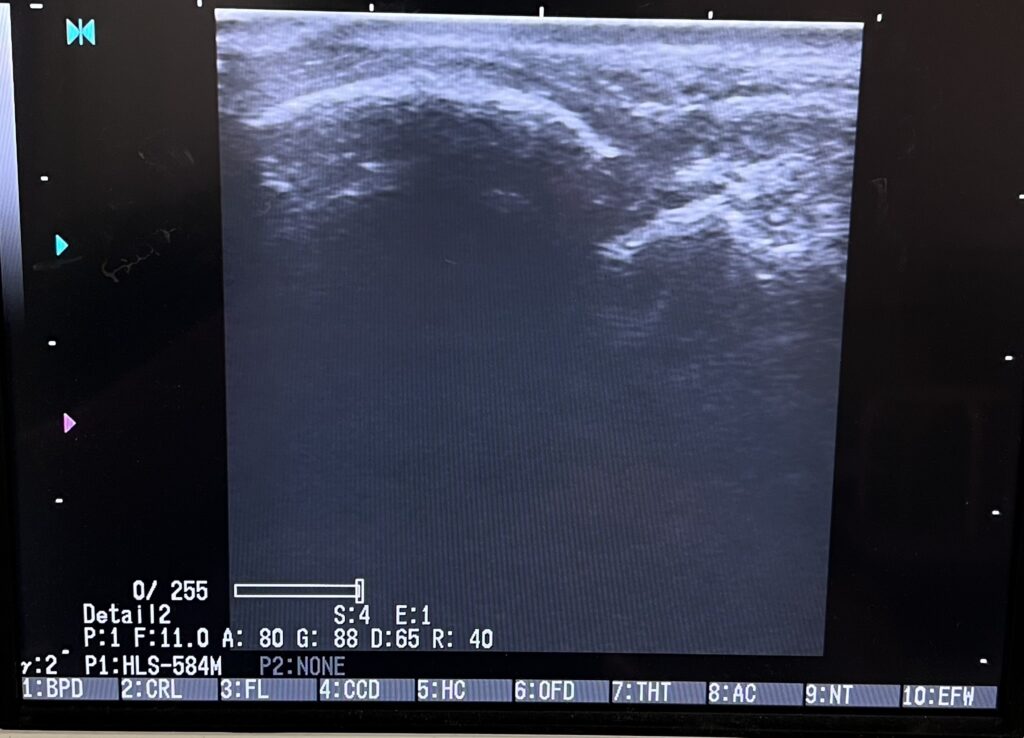

LIPUS(低出力パルス超音波)治療は、微弱な超音波を骨折部位に可能な限り毎日約20分照射することで、骨芽細胞を活性化し、骨の癒合を促進する物理療法です。

治療期間を約40%短縮する効果が期待でき、新鮮骨折から難治性骨折まで対応します。

さらには最近の研究では、軟部組織の組織回復にも有効と証明されています。